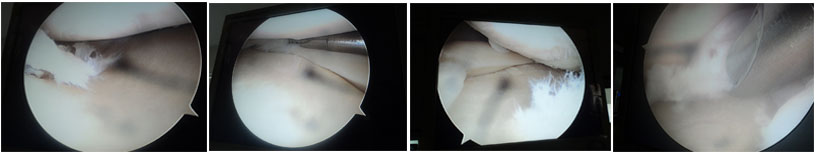

Knee arthroscopy is a minimally invasive procedure used to diagnose and treat ligament injuries, cartilage damage, and other knee problems. It ensures faster healing and a quicker return to normal activities.